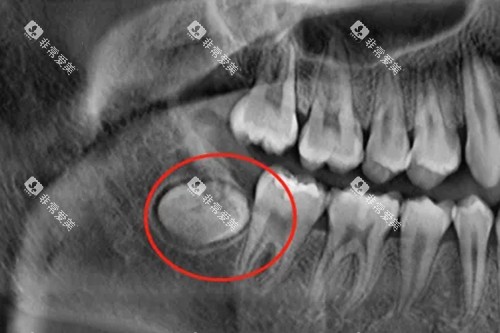

X光片显示智齿已导致邻牙牙根吸收或龋坏,拖延只会加重损害;

影像检查:

首当其冲的是全景片或CBCT检查,这些影像能清晰显示智齿与神经管的三维关系,帮助医生规划较佳手术路径。

临床数据显示,术前影像检查可使手术并发症降低40%。